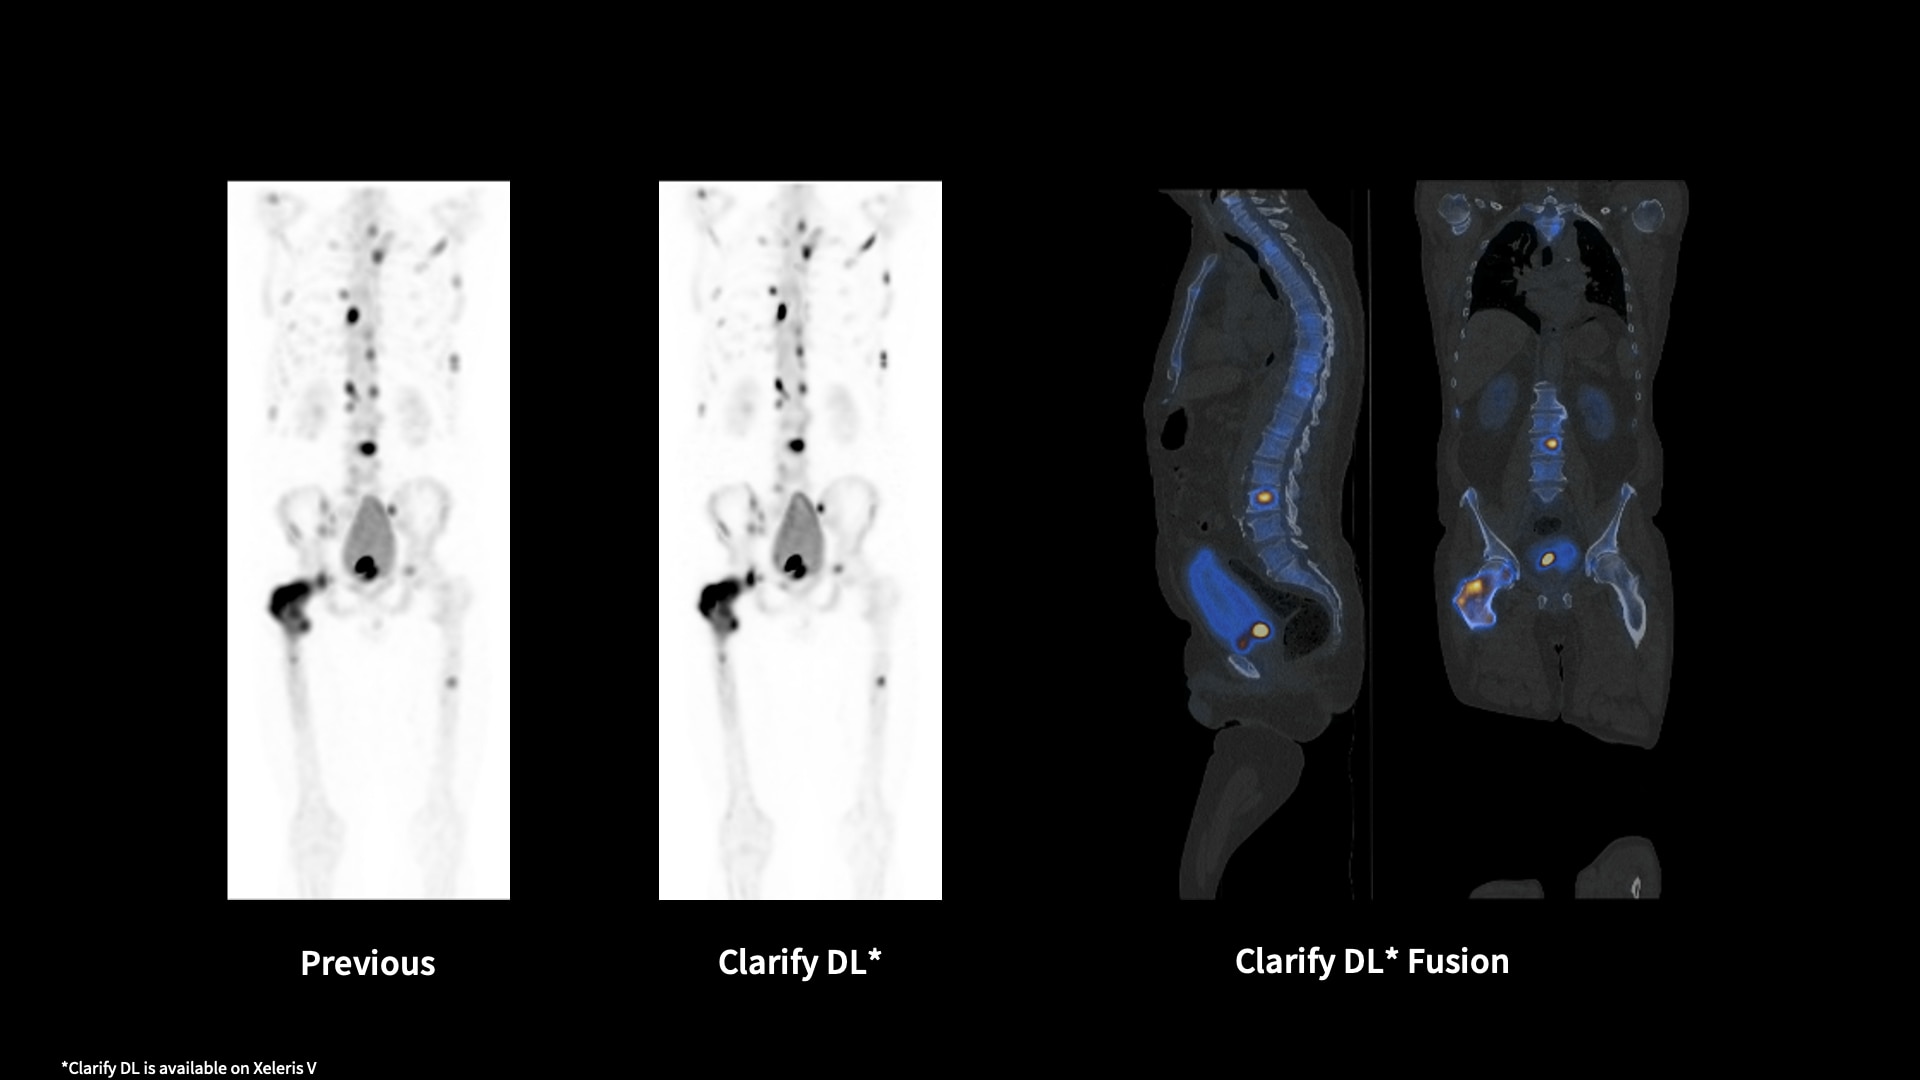

Clarify DL¹

Refocus with Clarify DL and move on from reading around the noise

Image quality has always required a trade-off between removing noise and maintaining contrast. GE HealthCare has a solution that mitigates that trade-off. Clarify DL is Aurora's AI-enabled bone SPECT image reconstruction designed to reduce noise, while retaining signal contrast. Doing so improves contrast-to-noise ratio (CNR) and contrast recovery coefficients (CRC)⁴, which are important factors in lesion detectability. With or without CT, Clarify DL is designed to achieve a new level of image quality performance without having to increase injected dose or scan time. Improved image quality performance may help increase diagnostic confidence.⁵ Clarify DL’s image resolution has been rated as better in 98% of exams.⁶

1. Clarify DL is available on Xeleris V

4. Clarify DL improves contrast recovery coefficient (CRC) up to 82% and contrast to noise ratio (CNR) up to 58% as compared to use of GE bone SPECT factory reconstruction presets for dual head cameras.* CRC and CNR are important factors in lesion detectability. *CRC and CNR demonstrated using digital phantom with inserted lesions of known size, location, and contrast, for AC and NC images.

5. Clarify DL improves dual head cameras’ image quality performance measured by Structures Similarity (SSIM) – up to 8% improvement, Mean Squared Error (MSE) up to 76% improvement, and Peak Signal-to-Noise Ratio (PSNR) - up to 18% improvement, as compared to GE bone SPECT factory reconstruction presets*. Improved image quality performance may help increase diagnostic confidence. *Demonstrated using digital phantom simulations with inserted lesions of known size, location, and contrast, for AC and NC images.

6. In 127 exams rated by total of 9 physicians, in 98% of the exams, Clarify DL’s image resolution was rated as better than the existing factory reconstruction preset images.* *As demonstrated in clinical evaluation, where each exam was reconstructed with both Clarify DL and the existing factory reconstruction preset and evaluated by 3 of the physicians.